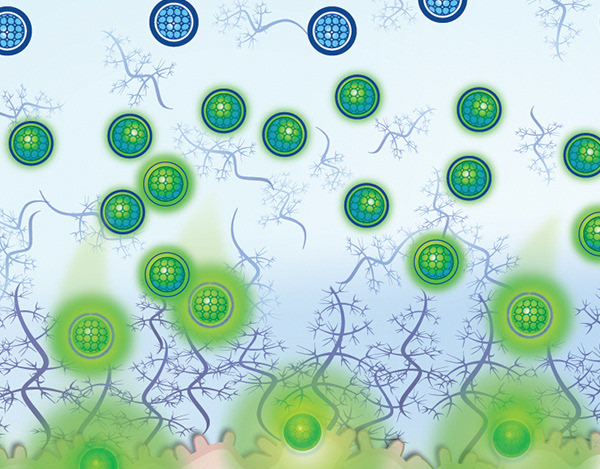

BioArt

Illustrating molecular method of action & drug delivery systems